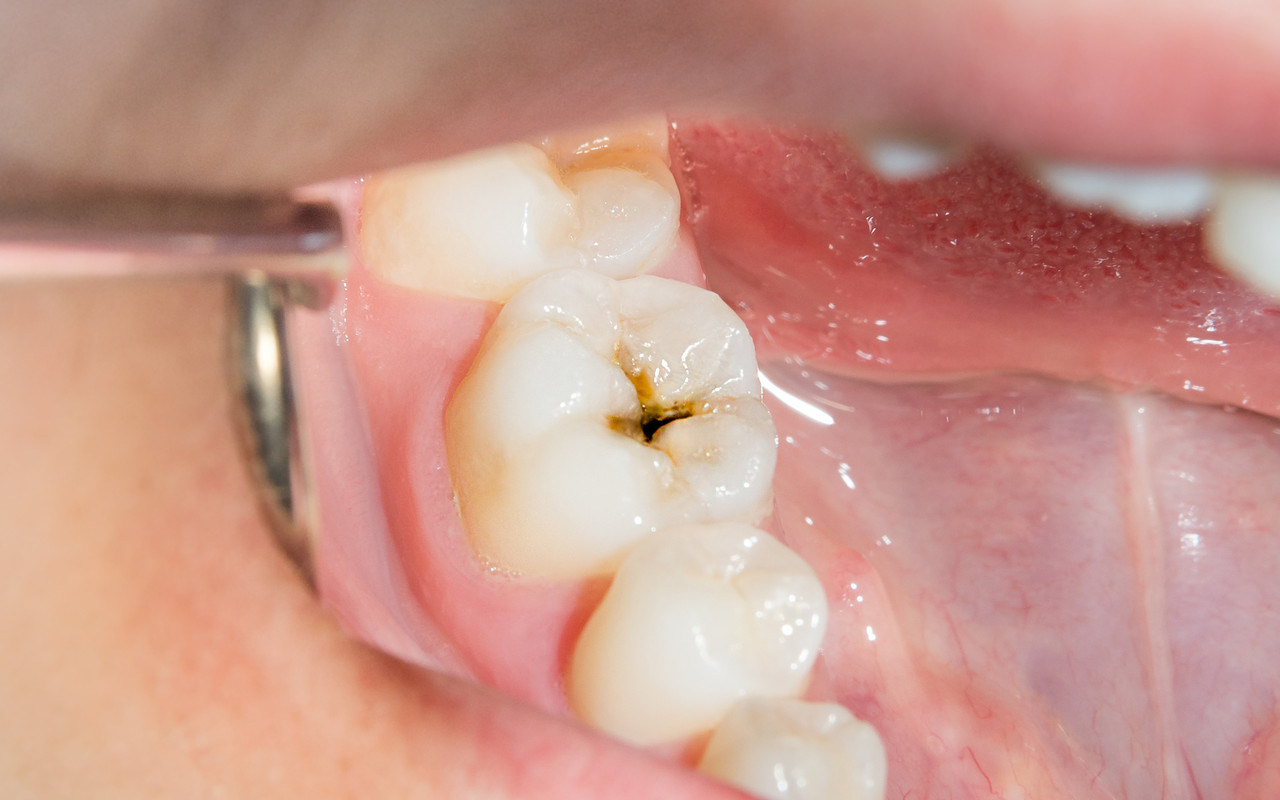

STEP 02. 충치 2단계

증상 : 충치가 상아질까지 침범한 단계입니다.

차갑거나 단 음식이 닿을 때 찌릿한 통증을

느낄 수 있습니다.

치료 : 충치 범위에 따라 레진으로 간단히 때우거나,

내구성이 더 좋은 인레이/온레이로 치료가

필요할 수 있습니다.

차갑거나 단 음식이 닿을 때 찌릿한 통증을 느낄 수 있습니다.

내구성이 더 좋은 인레이/온레이로 치료가 필요할 수 있습니다.